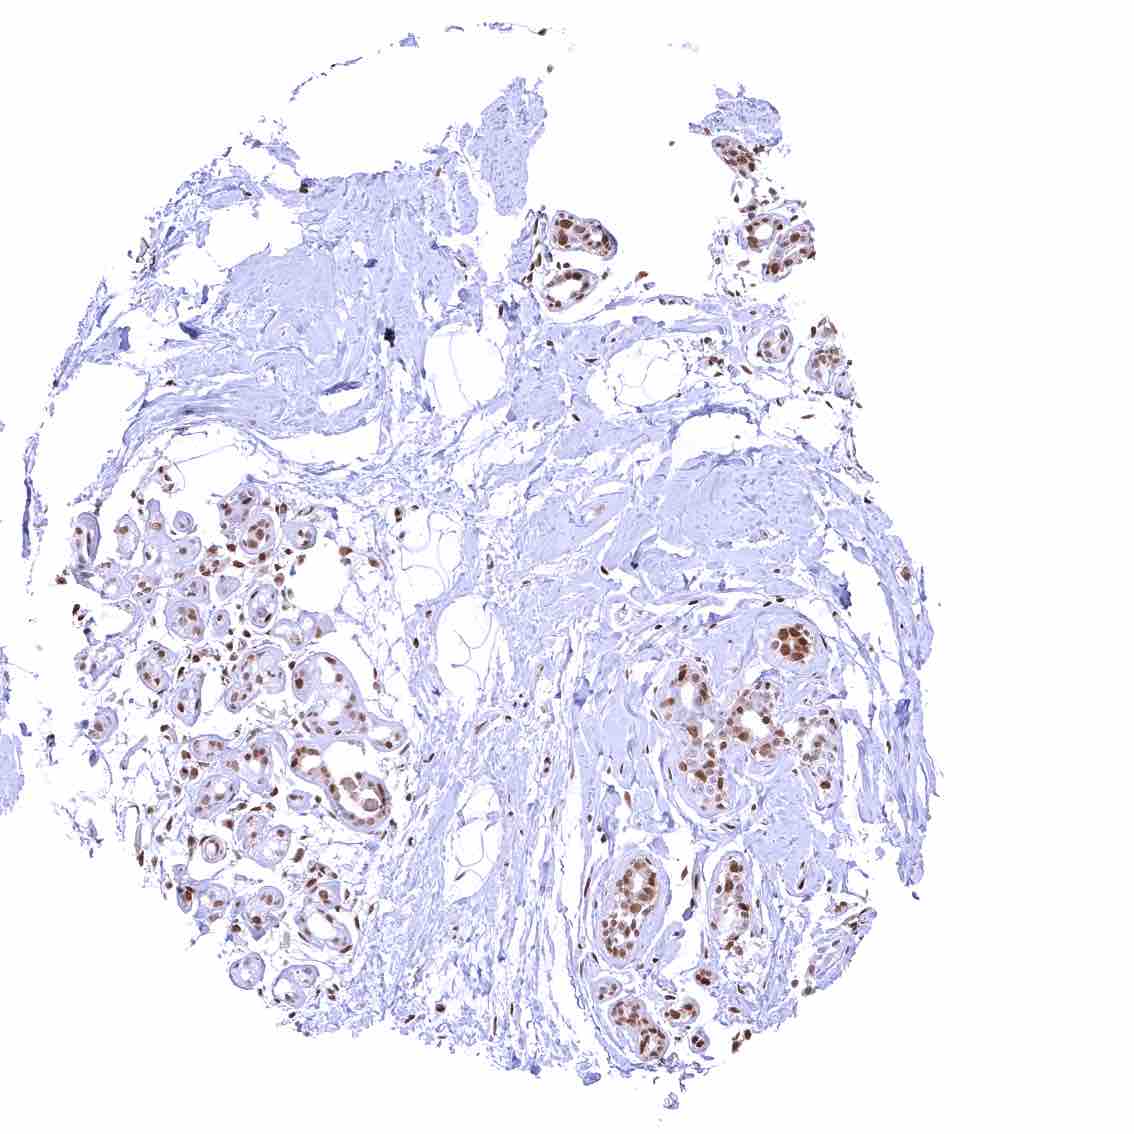

Prostate